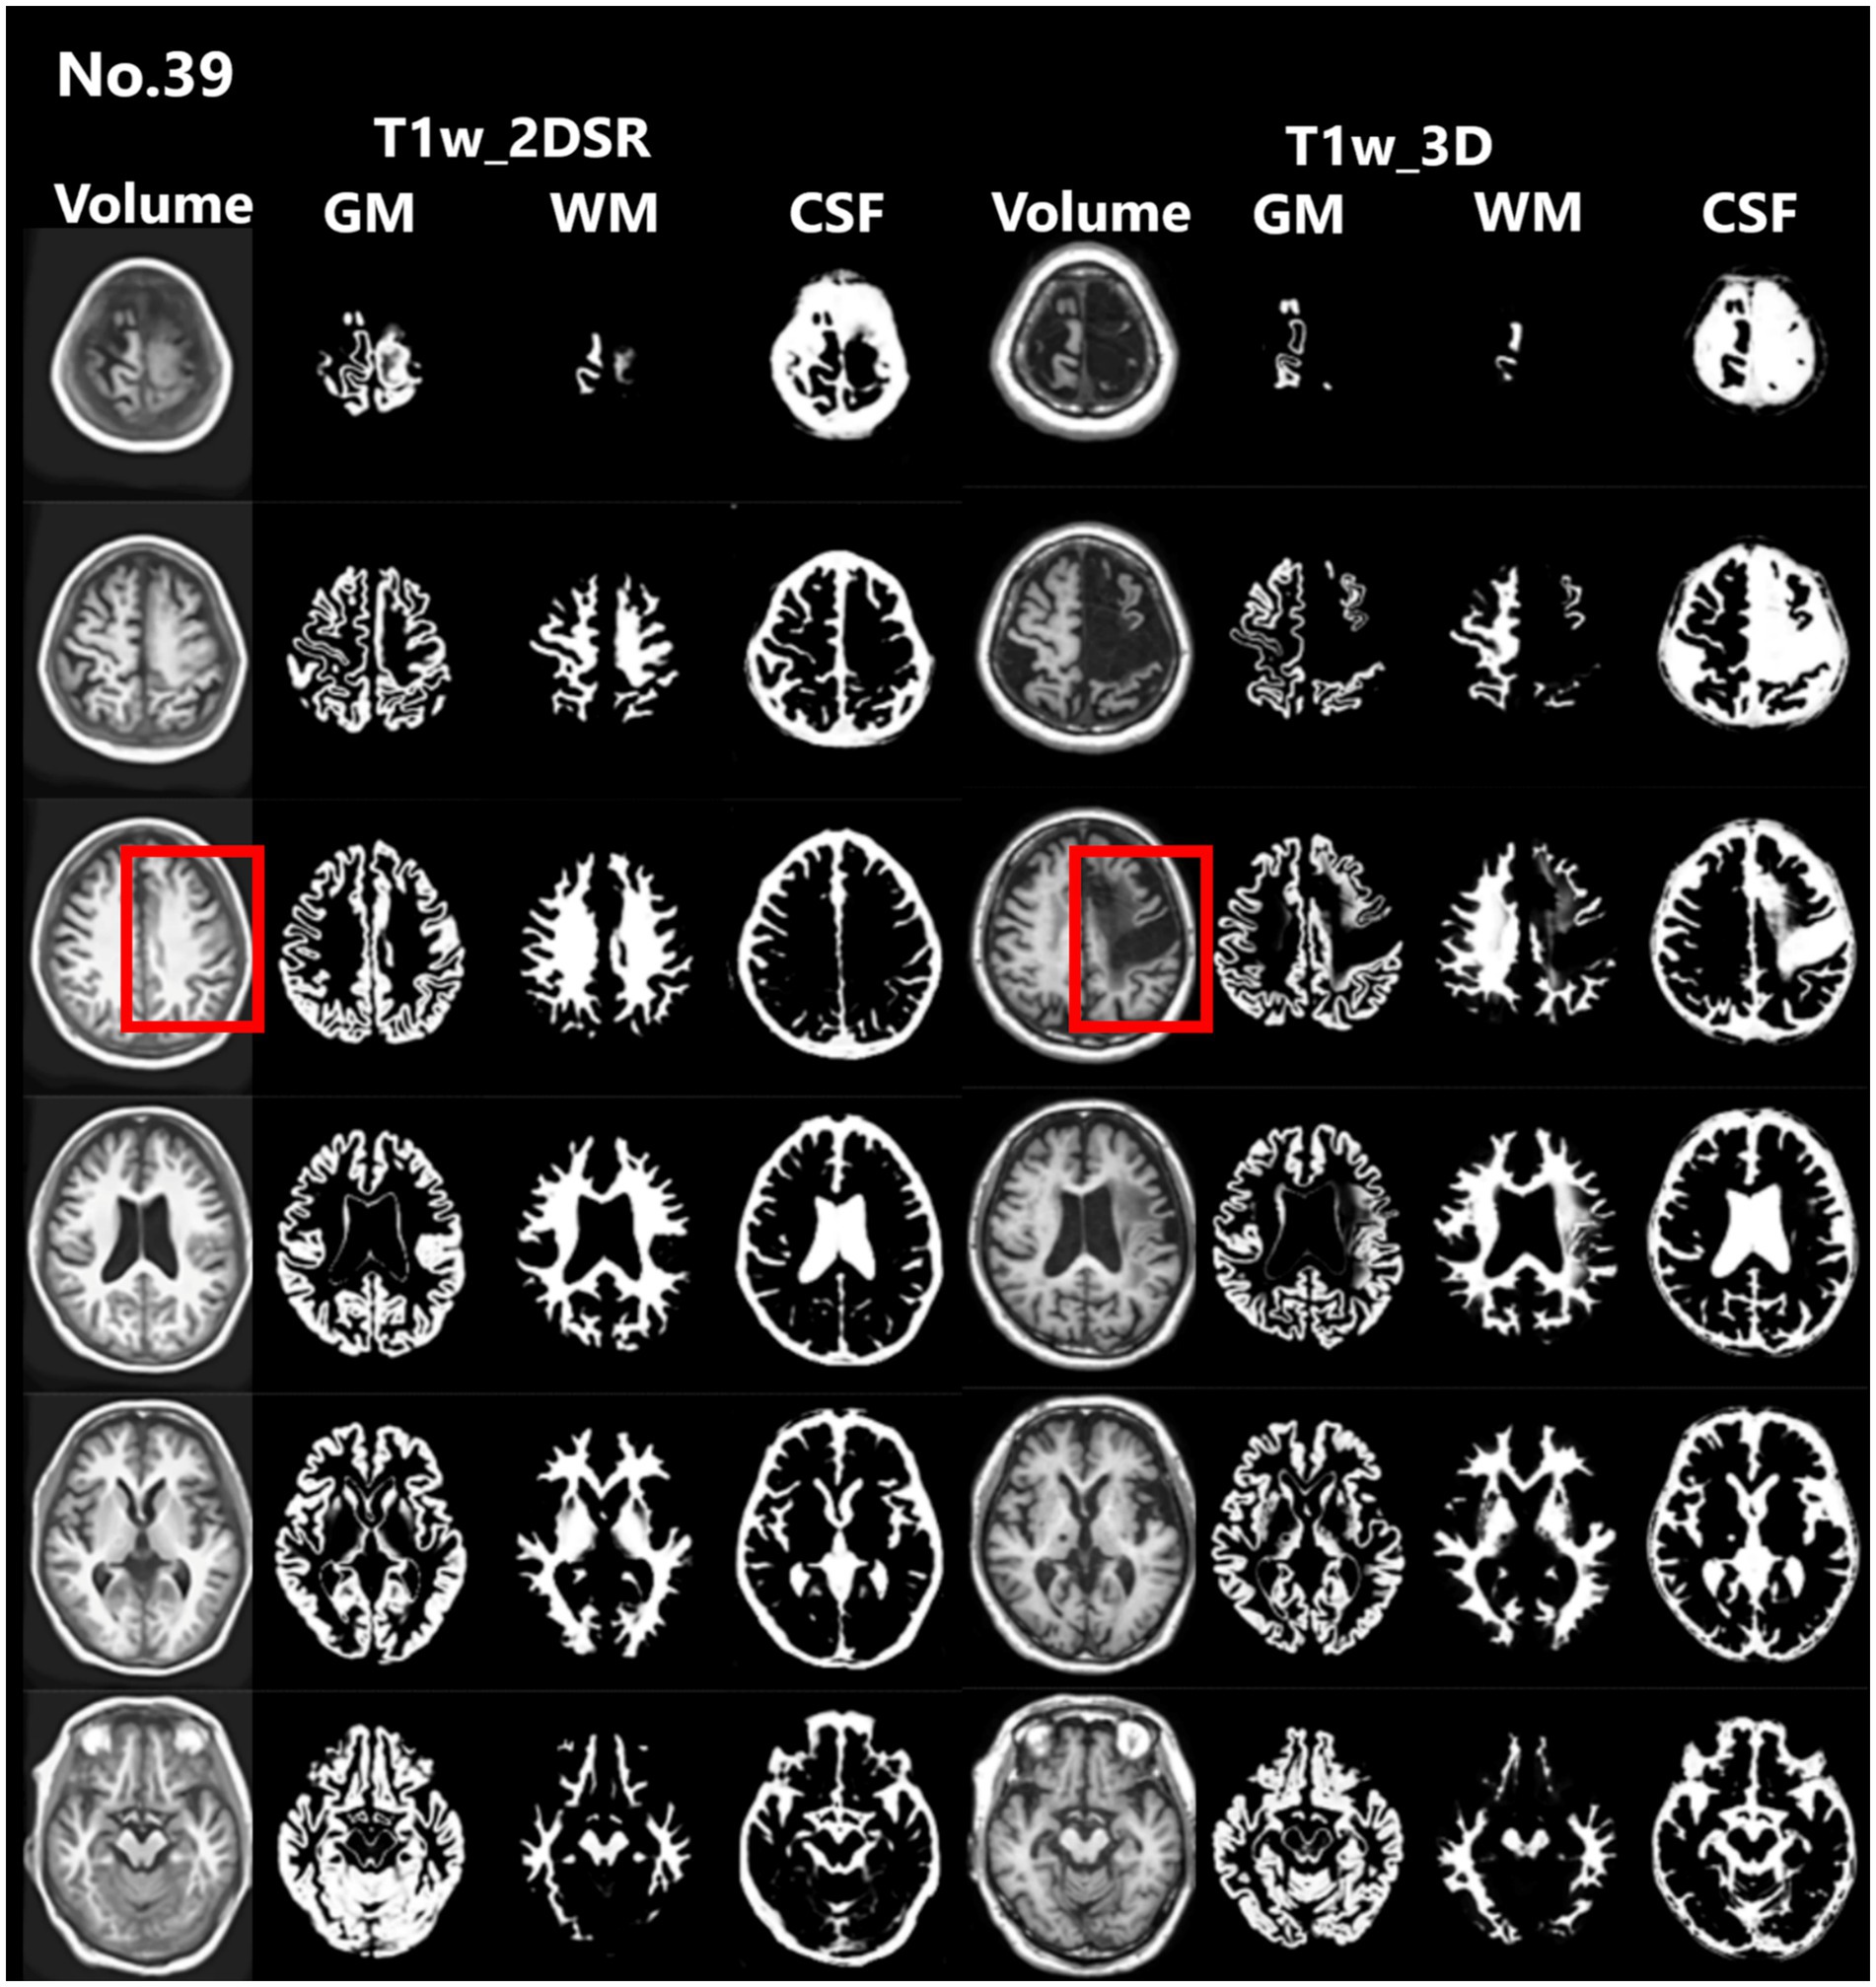

Seventy-five patients underwent MRI during the study period. Of these, 21 (28.0%) were male. The mean age was 83.5 years (range, 61–107 years). This cohort reflects the typical population undergoing dementia screening in Japan. For all cases, 3D volume data (T1w_2DSR) were successfully generated from T1w_2D using SynthSR. The generated T1w_2DSR did not reconstruct the parietal CSF region because it was not imaged in the original T1w_2D. Each output image was independently reviewed by two neurosurgeons. Cases with obvious motion artifacts and disrupted WM and GM segmentation in the control T1w_3D images were excluded from the analysis. Among the excluded cases, four (Cases 22, 26, 43 and 63) had showed segmentation errors involving the ventricles and GM due to brain atrophy (Figure 3), five (Cases 7, 11, 12, 69 and 72) showed segmentation failure caused by motion artifacts; and two (Cases 15 and 39) had structural brain lesions due to stroke (Figure 4). A total of 64 cases were analyzed after excluding 11 cases. After VSRAD analysis, four scores and three volumes were calculated. For these evaluated indices, normality was not met in most cases (Shapiro–Wilk test, p < 0.05), and thus non-parametric comparisons were adopted.

Figure 4. Representative excluded cases of stroke. Case no. 39 shows a patient with structural brain lesions due to stroke. In the 3D volume data acquired using the standard method, a low-signal area was observed in the left frontal lobe, consistent with cerebral infarction. In contrast, in the 3D volume generated by SynthSR, the lesion area appeared artificially filled in (red rectangles).